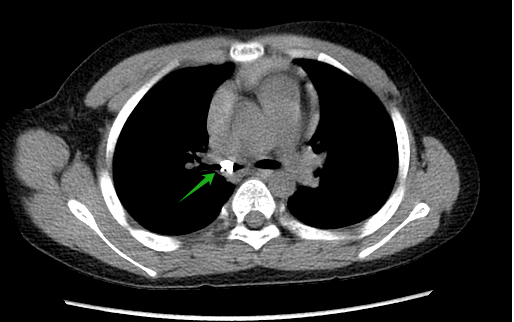

案例一

小曦,男,9岁,上体育课时突然龋齿脱落,随后出现呛咳,辗转多家医疗机构治疗3周,咳嗽无缓解,完善胸部CT检查发现右主支气管异物伴右侧阻塞性肺气肿,遂入院行“支气管镜气管异物取出术”,术中取出一颗龋齿,随后呼吸道症状缓解。

(绿色箭头为异物)

(气管镜下取出龋齿)